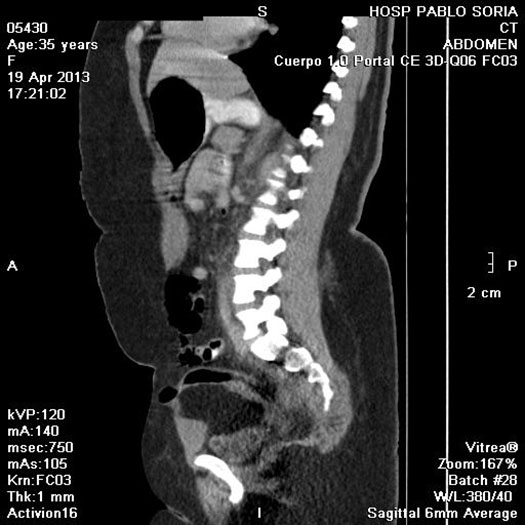

TAC

Paciente femenina, 45 años de edad, IMC > 35, (>) ingresa tras sufrir un accidente automovilístico por volcamiento. Sentada en el asiento de atrás con cinturón de seguridad a dos dedos en la cintura. Luego de 14hs del accidente ingresa al servicio de emergencia, lúcida, Glasgow 15, con dolor intenso en miembro inferior izquierdo y tatuaje de cinturón de seguridad a nivel de pelvis. Se realiza TAC de emergencia y se somete a una laparoscopia diagnóstica por descenso del Hto en 5 puntos. Se reconvierte a una laparotomía media , se sutura el mesosigma desgarrado y una laceración del sigma. Se constata hernia traumática con sección completa de pared anterolateral del abdomen. Se deja Abdomen abierto y contenido.